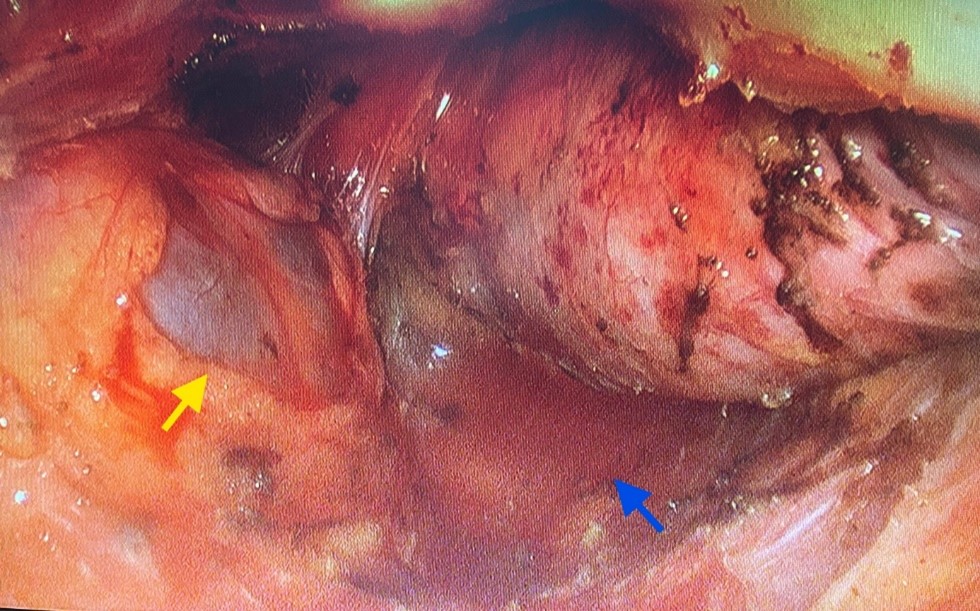

Exploration revealed no peritoneal effusion, no hepatic nodules, and no peritoneal carcinomatosis. After douglasotomy and extrafascial dissection of the rectum, multiple Tarlov cysts were identified, the largest on the left, and a tumor of the mid and lower rectum, more pronounced on the posterolateral right side, appearing to invade the posterior aspect of the uterus.

Figure 5: Laparoscopic image demonstrating the left Tarlov cyst (yellow arrow) after the extrafascial posterior dissection (blue arrow).